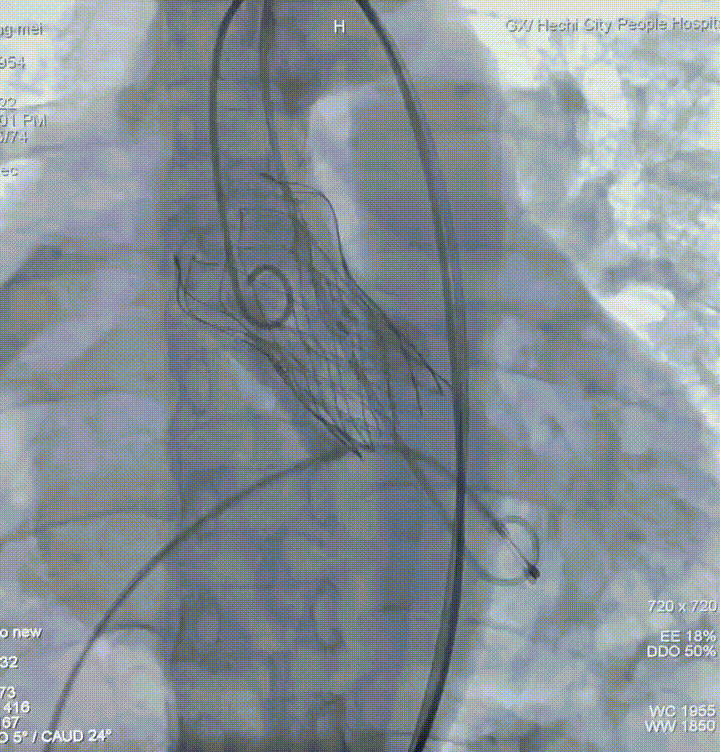

术中操作

二尖瓣球囊扩张

人工瓣膜在主动脉瓣处锚定释放后,工作正常,造影未见瓣周漏,零压差,二尖瓣瓣口面积从0.55cm²恢复至1.2cm²以上,患者血流动力学得到明显改善,手术圆满完成,患者苏醒后顺利转入病房。